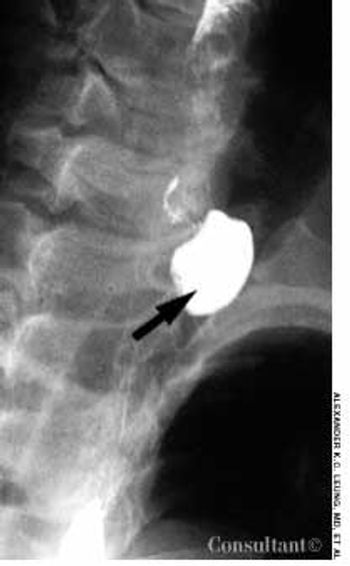

Alimentary tract duplications are uncommon. Gastric duplication accounts for only 3.8% of these duplications. The cause is not known, but faulty separation of the endoderm and notochord early in embryonal development is thought to be responsible. The anomaly occurs in twice as many female as male infants.

A 2-year-old boy was hospitalized because of acute abdominal pain. He had no other symptoms. The child's temperature was 37.3°C (99.1°F). He was irritable and had generalized abdominal tenderness. A stool test was positive for blood. Results of laboratory investigations were normal.